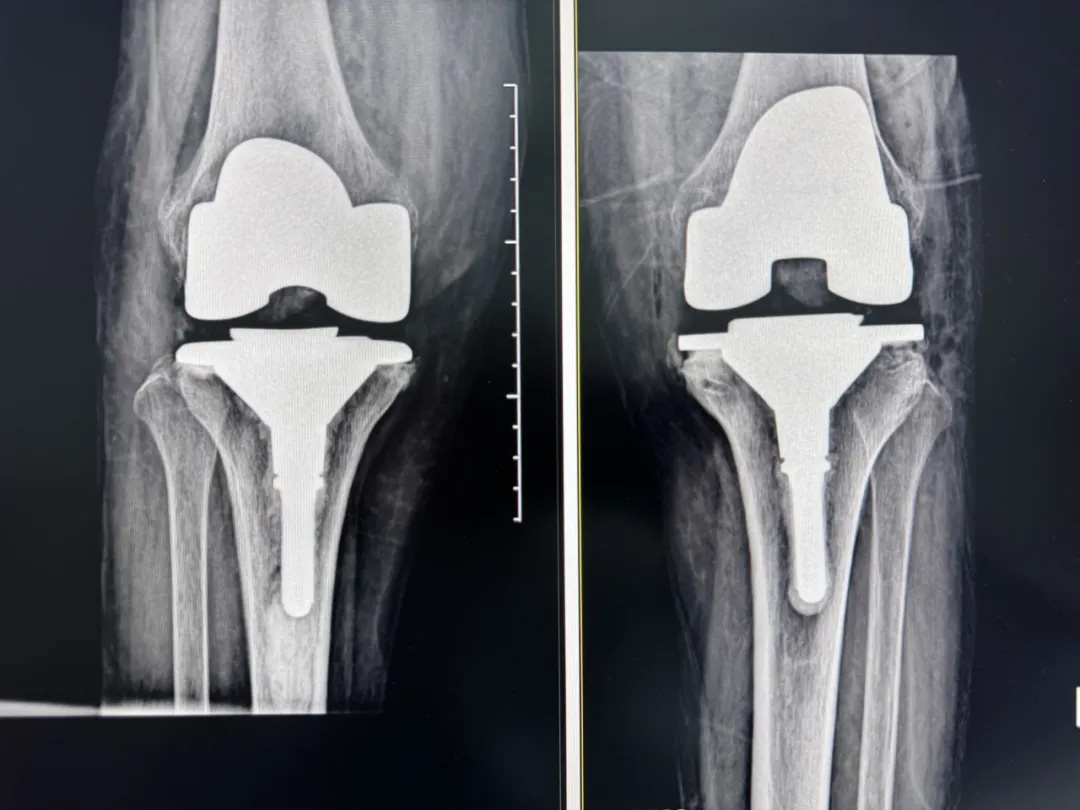

術(shù)前:AI通過(guò)CT掃描生成毫米級(jí)膝關(guān)節(jié)三維模型,為假體安裝設(shè)計(jì)出誤差小于1毫米的精準(zhǔn)方案 術(shù)中:智能導(dǎo)航系統(tǒng)如同"透視眼",引導(dǎo)醫(yī)生避開(kāi)密集的神經(jīng)血管網(wǎng),截骨更精準(zhǔn),出血僅100ml 術(shù)后:當(dāng)天鄭阿婆即開(kāi)始抬腿的康復(fù)訓(xùn)練,24小時(shí)內(nèi)扶助行器下地行走,三天后已能在病房走廊獨(dú)立行走,完成洗漱用餐 兩周后健步出院時(shí),女兒含淚感慨“之前擔(dān)心她年紀(jì)大扛不住手術(shù),沒(méi)想到恢復(fù)這么快!現(xiàn)在每天散步比我還精神。知道技術(shù)這么先進(jìn),真該早點(diǎn)來(lái)!”

"這就像給傳統(tǒng)手術(shù)裝上了自動(dòng)駕駛系統(tǒng)。"主刀醫(yī)生羅軍副院長(zhǎng)用生動(dòng)比喻解析技術(shù)突破。AI不僅實(shí)現(xiàn)假體“量身定制”,使用壽命可達(dá)20年以上,更通過(guò)三維路徑規(guī)劃將康復(fù)周期壓縮,實(shí)現(xiàn)術(shù)后24小時(shí)下地,2周回歸正常生活。同時(shí),AI會(huì)避開(kāi)重要組織,具有出血少、感染風(fēng)險(xiǎn)低的特點(diǎn)。專家特別提醒,當(dāng)出現(xiàn)夜間持續(xù)性關(guān)節(jié)疼痛、步行能力低于10分鐘或關(guān)節(jié)畸形時(shí),應(yīng)及時(shí)就醫(yī)評(píng)估,"別等到關(guān)節(jié)'報(bào)廢'才手術(shù)"。